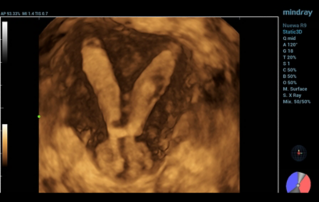

![ultrasonic-diagnosis-mullerian-duct-anomalies.thumb.319.319 Ultrasound Journal 39 - Ultrasonic Diagnosis of M├╝llerian Duct Anomalies]() Ultrasound Journal 39 - Ultrasonic Diagnosis of M├╝llerian Duct AnomaliesHow 3D transvaginal ultrasound replaced MRI for detecting uterine malformations. Septate uterus case demonstrates Smart ERA's role in reproductive imaging. Evidence-based diagnosis.Ultrasound Cases | Ultrasound | Smart applications | OB GYN 2025-12-04

Ultrasound Journal 39 - Ultrasonic Diagnosis of M├╝llerian Duct AnomaliesHow 3D transvaginal ultrasound replaced MRI for detecting uterine malformations. Septate uterus case demonstrates Smart ERA's role in reproductive imaging. Evidence-based diagnosis.Ultrasound Cases | Ultrasound | Smart applications | OB GYN 2025-12-04 -